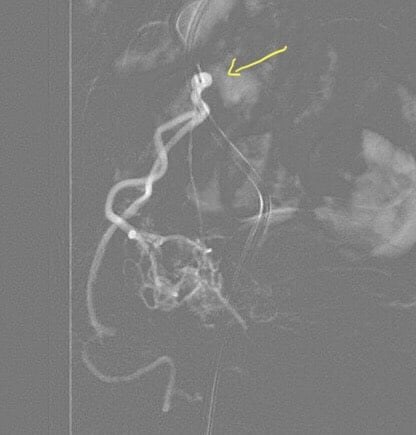

Mô tả lại tiến trình can thiệp, BS Giang vẫn còn cảm thấy hạnh phúc bởi kíp kỹ thuật đã tạo nên một kỳ tích trong lịch sử y học Việt Nam và cũng chưa từng có trong y văn thế giới. “Khi thực hiện nút mạch cho bệnh nhân, sau khi hoàn thành 1 bên hoàn toàn tốt, chúng tôi thực hiện bên còn lại thì gặp khó khăn do 3 gốc động mạch tuyến tiền liệt, động mạch bàng quang dưới, động mạch bàng quang trên được tách ra cùng vị trí của động mạch chậu trong tạo thành ngã tư rất khó chọn lọc vào động mạch tuyến tiền liệt. Sau những phút nỗ lực cực điểm để tiếp cận được nhánh này thì chúng tôi lại còn ngỡ ngàng hơn, khi động mạch tuyến tiền liệt rất bé, ngắn, lại còn xoắn đúng 1,5 vòng. Với sự thành thạo kỹ thuật của kíp can thiệp, cùng với việc sử dụng khéo léo các vi ống thông và vi dây dẫn siêu nhỏ cỡ dưới 0.010”, kíp can thiệp đã thành công để có thể đi qua được “vòng xoắn” đó và tiếp cận siêu chọn lọc động mạch tuyến tiền liệt.

| Chụp động mạch chậu trong cho thấy động mạch tuyến tiền liệt tách ra từ vị trí khó | Hình ảnh cho thấy động mạch tuyến tiền liệt tách ngay gần động mạch bàng quang trên, dưới đồng thời xoắn 1,5 vòng | Động mạch tuyến tiền liệt sau khi qua được vị trí khó khăn | Chụp mạch kiểm tra lại sau gây tắc hoàn toàn bằng hạt và tắc gốc bằng keo histoacryl |